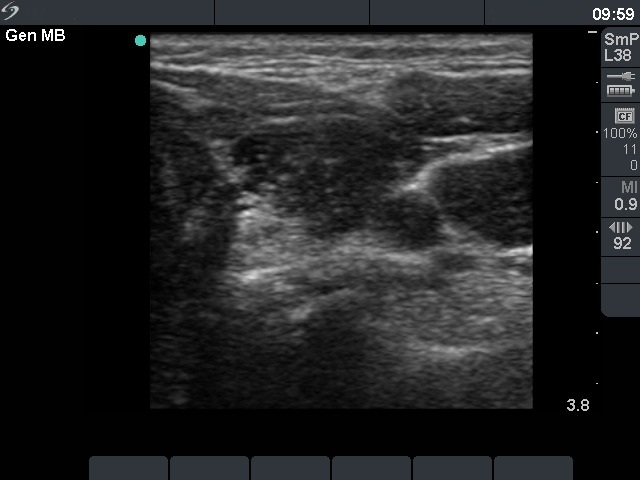

Ultrasonography. The thyroid was echonormal and presented several hypoechoic areas. The pattern in the right lobe was obviously focal form of lymphocytic thyroiditis.

A relatively large hypoechoic areas was found in the left lobe. The lesion had irregular borders. At first sight, this presentation of the left lobe could be interpreted as the central hypoechoic area-type form of lymphocytic thyroiditis. However, the hypoechoic lesion was not entirely surrounded with echonormal thyroid tissue. More importantly, the central hypoechoic areas-type form is almost always bilateral.

The sonographic pattern is remarkable. On the one hand, the tumor was identical to other more active foci of Hashimoto's thyroiditis. The only difference was the size of this lesion which was larger than other lesions observed in the thyroid. In the case of Hashimoto's thyroiditis neither the irregularity of border, nor the increased vascularization has any relevance. On the other hand, the tumor had microcalcifications and was significantly larger than other foci. The lesson to draw is the comparison of various lesions: if we detect a lesion which differs from others regarding the echogenicity, the size or the vascularization, it is advisable to perform FNA.

The distinction of central hypoechoic area-type form of LT from a large hypoechoic nodule is in part based on noticing whether the pattern is bilateral or unilateral. While the former is almost pathognomonic of LT, the latter excludes this special form of LT and significantly increases the probability of a true nodule.